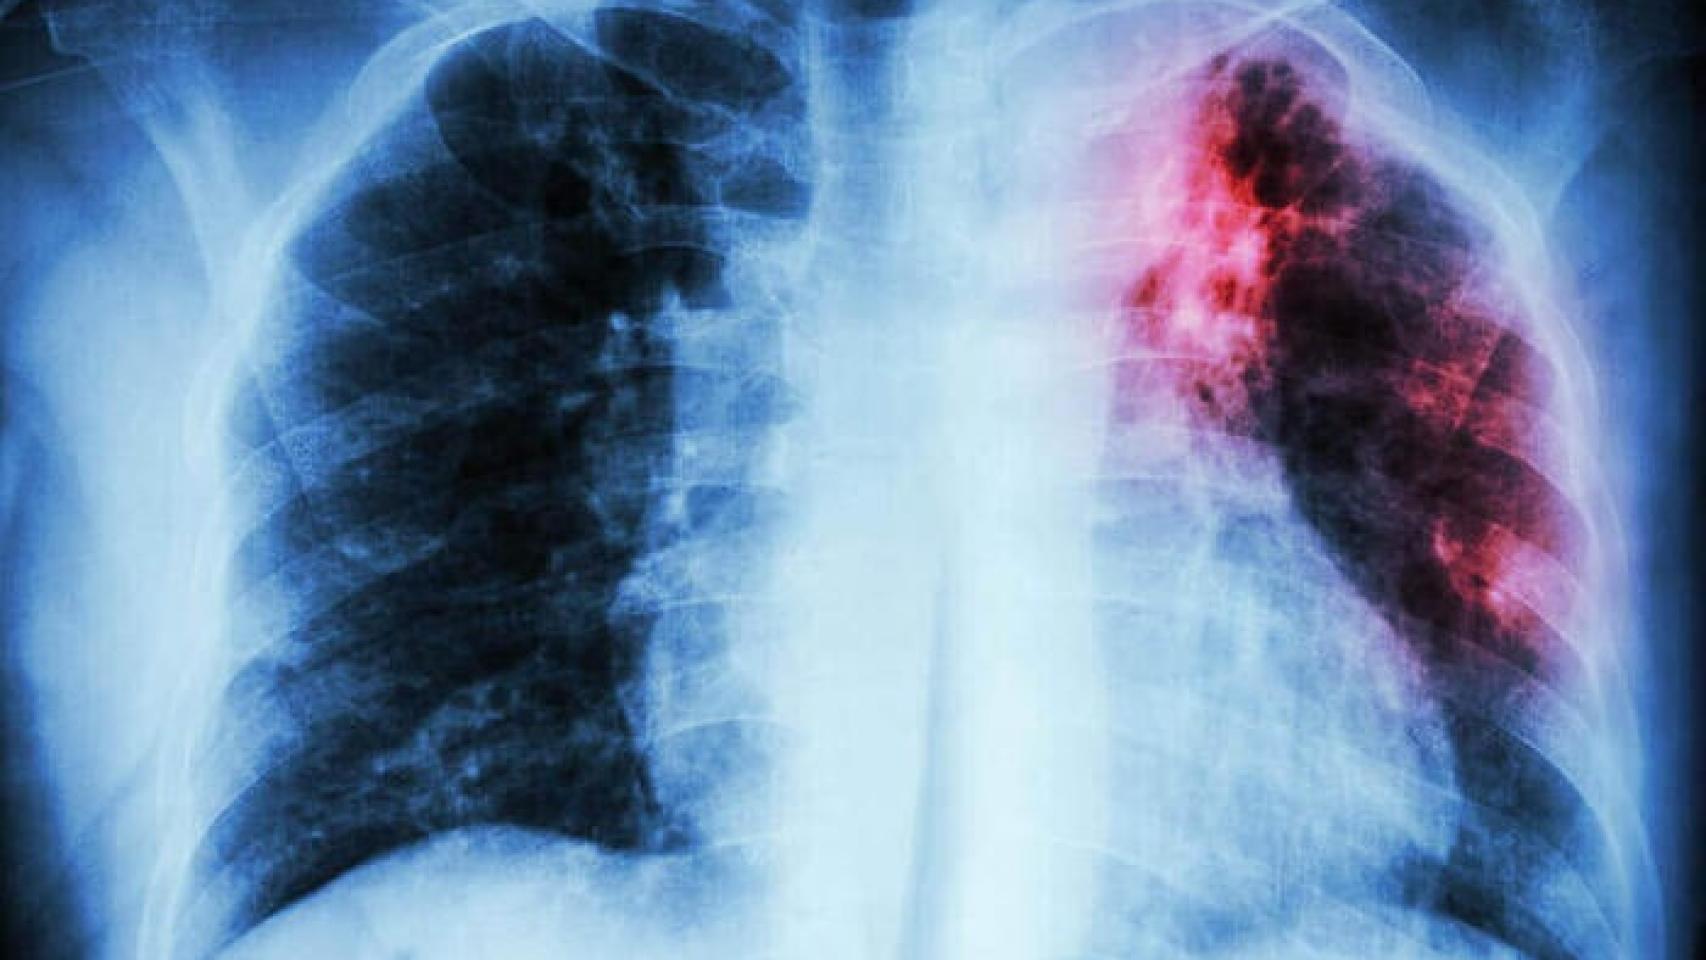

Tras analizar específicamente las tasas de mortalidad por cáncer de pulmón en cinco países de la UE y Reino Unido, se calculó que la mortalidad en mujeres aumentará casi un 14% en Francia, un 5,6% en Italia y un 5% en España. Si bien es cierto que la mortalidad disminuirá en las mujeres de entre 25 a 64 años, se ha identificado que el aumento se producirá en los grupos de 65 a 75 años, y a partir de los 75. El resultado será un aumento general de la tasa.

Según explican los investigadores, estas diferencias se deben al momento de dejar de fumar. Las mujeres que tienen entre 45 y 65 años han consumido menos tabaco. Sin embargo, las mayores llegaron a fumar hasta 20 años más de media, empezando en los setenta, cuando el tabaquismo era más frecuente en mujeres jóvenes. Cabe destacar que en Reino Unido sí se produciría una caída del 13,8% de la mortalidad por cáncer de pulmón en mujeres, pero parte de una base superior a la de la UE: 16,2 casos por cada 100.000. Mata a más mujeres británicas que el cáncer de mama, con tasas de mortalidad de 13,5 por cada 100.000.

Este estudio "recalca la importancia que tienen determinados hábitos sociales en la incidencia de algunos tipos de cáncer, como son el tabaquismo o los malos hábitos alimentarios y el poco ejercicio físico que conducen a la obesidad", declara a SMC España Xosé R. Bustelo, profesor de investigación del CSIC, vicedirector del Centro de Investigación del Cáncer, Salamanca, y expresidente de ASEICA. "Y, en el caso de España, ese mensaje es claro: es uno de los pocos países en donde se predice que aumentarán las muertes por cáncer de pulmón en mujeres en franjas de edades que son consistentes con la frecuencia de mujeres fumadoras".